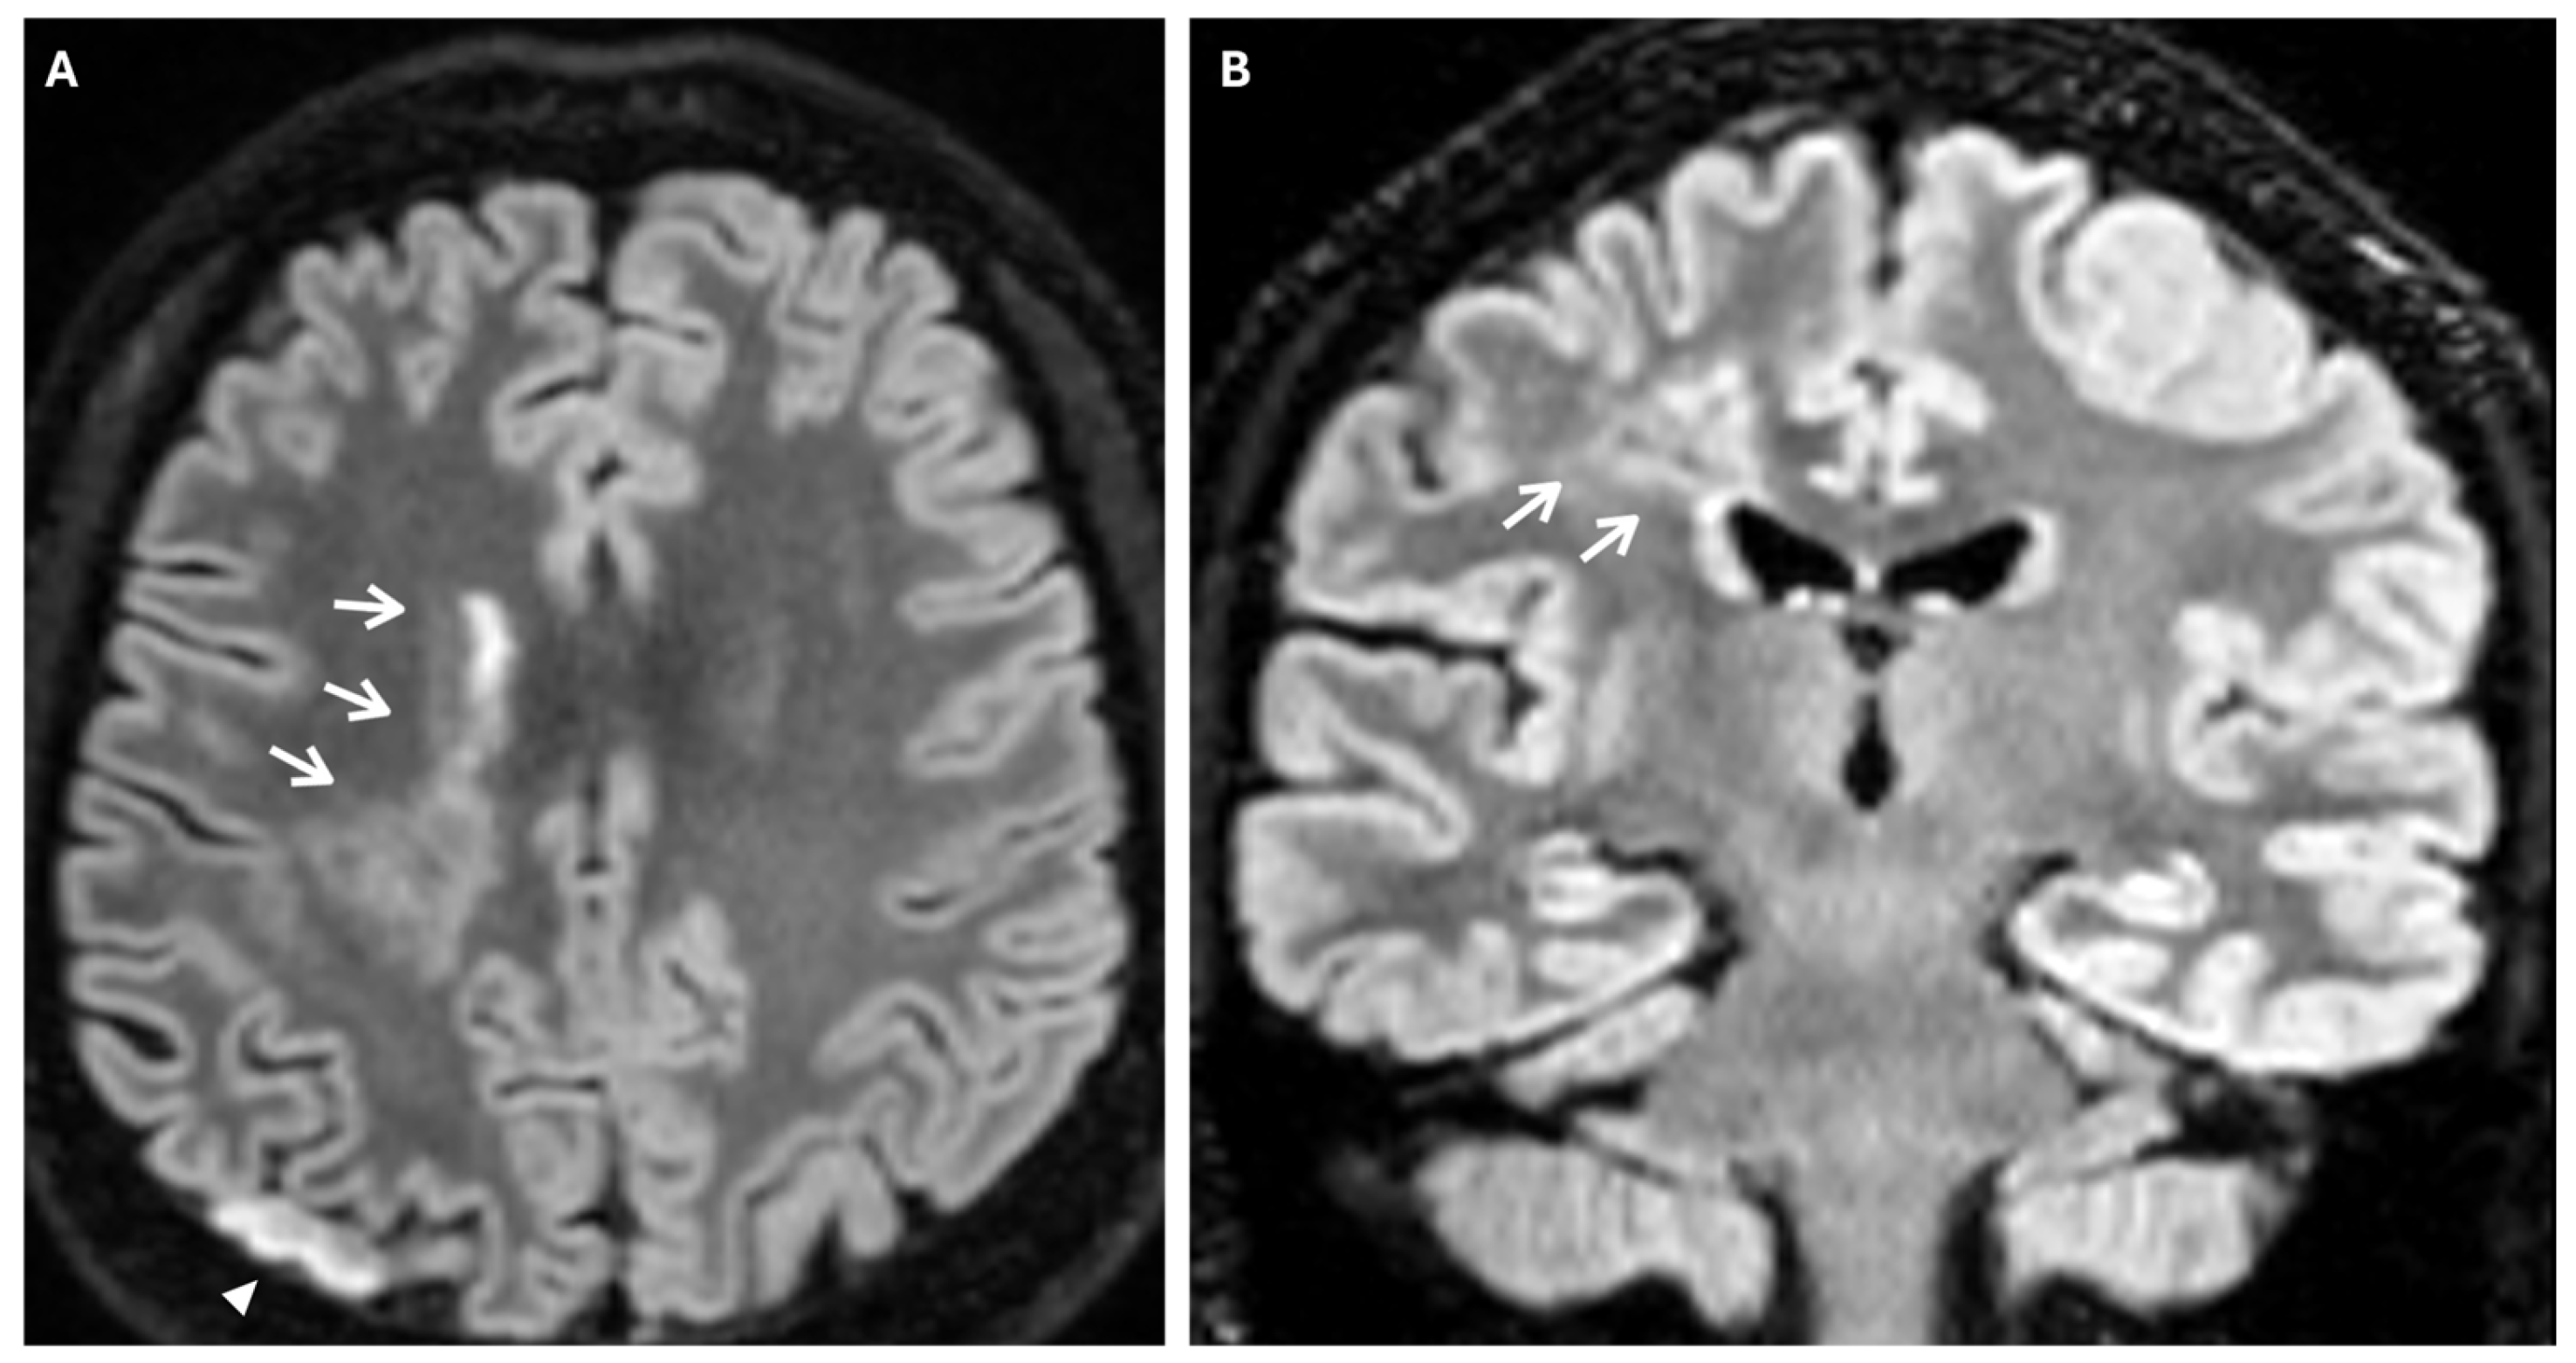

Another phenomenon that can be observed on FLAIR sequences is the “medullary streak” sign, which is characterized by a hyperintense streak oriented perpendicularly to the lateral ventricle (“periventricular medullary veins/FLAIR hyperintense streaks”); despite its etiology remaining ambiguous, the condition has been associated with ischemia and could represent collateral vasculature, stagnated cerebrospinal fluid, or vasogenic edema (Figure 7).

Figure 7. Axial (A) and coronal (B) 3d FLAIR sequences show a hyperintense streak area oriented perpendicularly to the right lateral ventricle (white arrows), representing the “medullary streak” sign. Note the right parietal subacute ischemic lesion (white arrowhead).

Approximately half of adult patients with MMD may develop intracranial hemorrhage. The location of the hemorrhage can be subarachnoid, intraventricular, or intraparenchymal, more often within the basal ganglia [3]. Microbleeds can be detected through the use of gradient echo T2* sequences or susceptibility-weighted imaging (SWI), the latter being a 3D gradient-echo sequence with an increased spatial resolution and higher sensitivity to these alterations. Microbleeds may be associated with leakage from dilated and fragile collateral vessels, such as the anterior choroidal or posterior communicating arteries. These alterations also have a prognostic value, as they indicate an increased risk for intraventricular hemorrhage, particularly if located in the periventricular area [2]. In fact, rupture of prominent and fragile anterior choroidal arteries leads to intraventricular hemorrhage, as often observed in MMD [22]. Furthermore, SWI and FFE sequences can detect prominent medullary veins, identifying hypointense blooming artifacts within multiple intracranial blood vessels (“prominent vessel sign”). This sign reflects an increased concentration of paramagnetic deoxyhemoglobin in cortical veins (referred to as the “cortical vein sign”), subependymal and medullary veins (referred to as the “brush sign”) (Figure 8), and it is associated with an increased risk of infarction, low cerebral blood flow (CBF), and low cerebrovascular reactivity [17,23].

Figure 8. (A) Axial FFE sequence shows subependymal and medullary veins bilaterally, representing the “prominent vessel sign” (white arrowheads). (B) Magnification of the previous image illustrates deep medullary veins on the left hemisphere (wavy black lines).